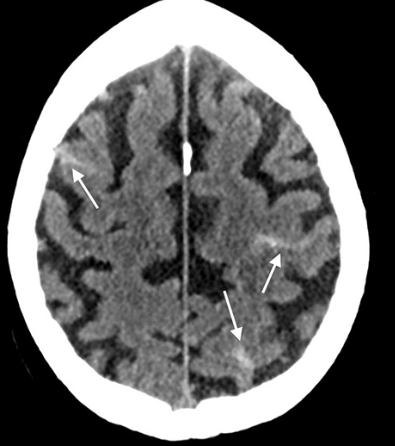

What is subarachnoid haemorrhage, and what does it look like on CT head?

A

Subarachnoid haemorrhage: Blood collection between arachnoid mater (middle lining of brain) and pia mater (inner lining of brain), in the subarachnoid space (CSF, cisterns, fissures/sulci)

CT finding: Hyperdense lesions in CSF-filled areas eg. Sulci (grooves), cisterns (outpouchings of subarachnoid space)